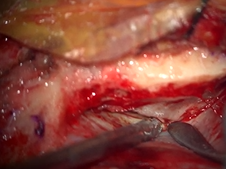

Transcervical Exploration of Parapharynx for Deep Lobe Parotid Pleomorphic Adenoma

- Date : 01/01/2020